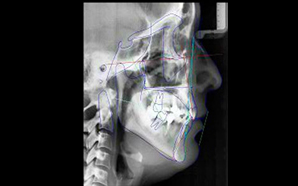

SERVICIOS